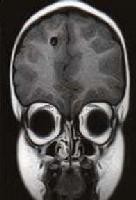

Khi ấu trùng cư trú ở mắt gây các triệu chứng chèn ép sau nhãn cầu, tăng nhãn áp, giảm thị lực, song thị,…

+Chụp cắt lớp vi tính (CT Scanner) não tìm các hình ảnh đặc hiệu (các nang sán là những nốt dịch có chấm mờ, kích thước 3-5mm, đôi khi nang có kích thước lớn đến 10mm, rải rác có nốt dạng vôi hóa);